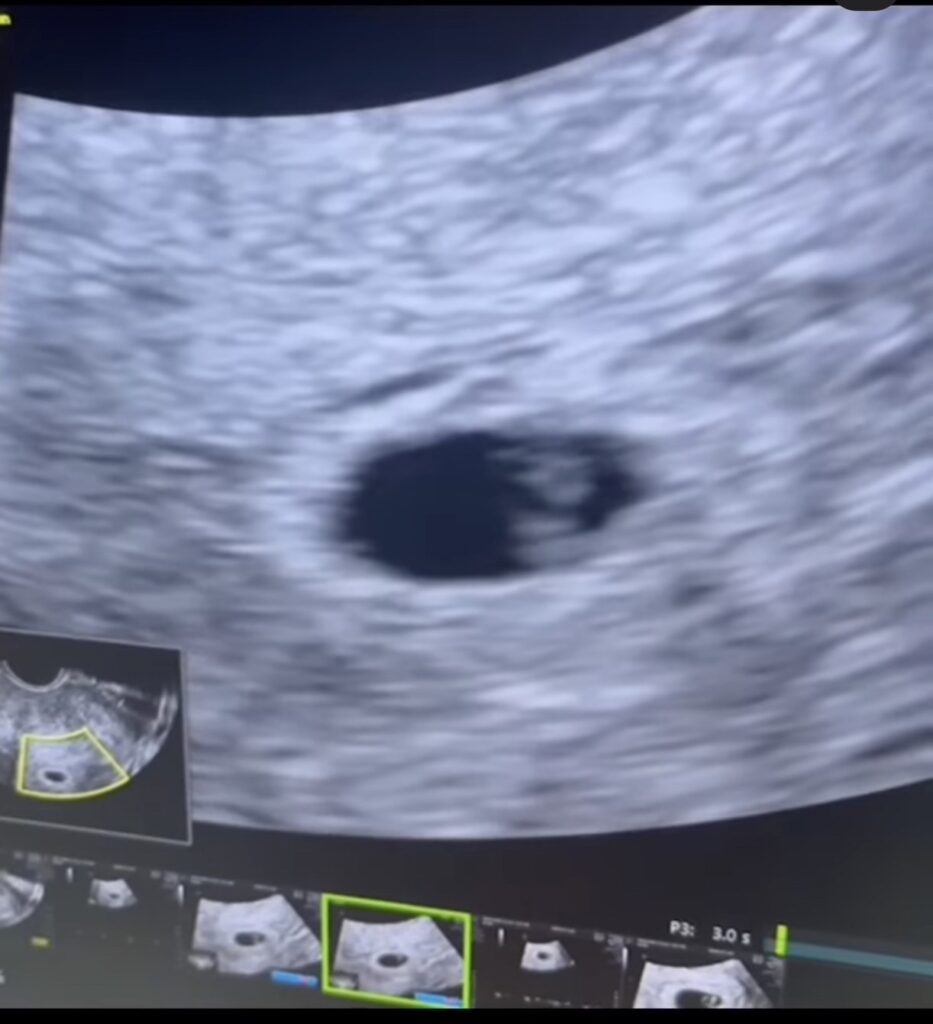

ล่าสุดแฟนๆเฮลั่น เมื่อสาวยุ้ยได้ออมาประกาศข่าวดีขึ้นแท่นเป็นคุณแม่ป้ายแดงแล้ว โดยเจ้าตัวออกมาโพสต์ภาพโชว์ที่ตรวจครรภ์ขึ้น2ขีด ที่แปลว่าท้อง พร้อมแคปชั่นว่า”เธอ+ฉัน = เรา 3 คน ทุกปาฏิหาริย์ต้องใช้เวลา…เบบี๋น้อยของเรามาแล้วน๊าาา ดีใจที่สุด… มีความสุขที่สุดเลย”